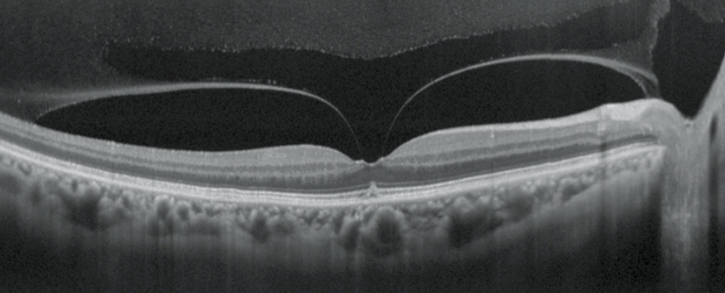

視網(wǎng)膜分析

OCT靈敏度可選

根據(jù)病歷,通過選擇適宜的OCT靈敏度,以確保對(duì)介質(zhì)渾濁患者的圖像采集。

高清追蹤plus功能

高清追蹤plus功能可追蹤無意識(shí)的眼球運(yùn)動(dòng),在SLO圖像上保持相同的掃描位置,確保精確的圖像采集。此功能可獲得多至120張疊加的高清圖像。